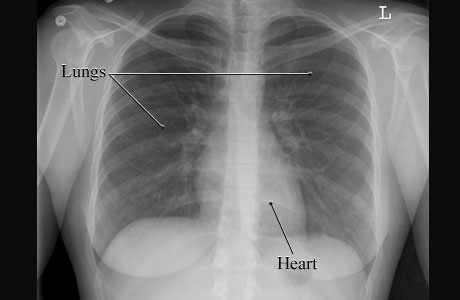

X-Ray of a Normal Chest

This is a picture of a normal chest X-ray of a woman showing the air-filled spaces of the lungs and the more solid gray shape of the heart. The lungs and heart are normal in size and shape.